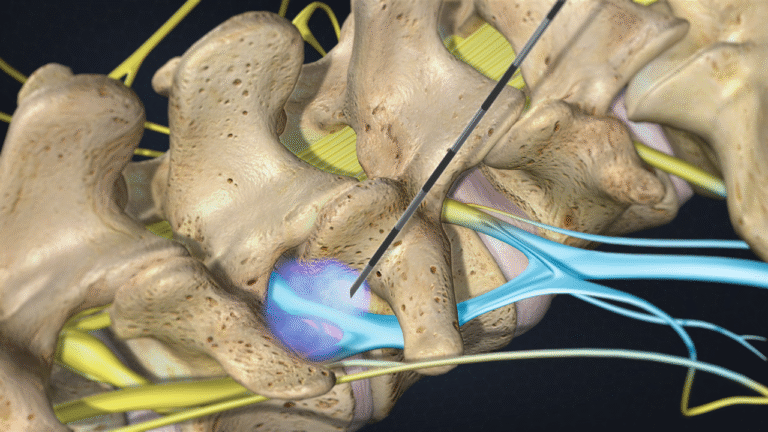

- Minimally invasive procedures

Back pain

Il dolore lombare è una condizione molto frequente. Può avere diverse cause, come problemi muscolari, articolari o discali, e spesso limita le attività quotidiane.